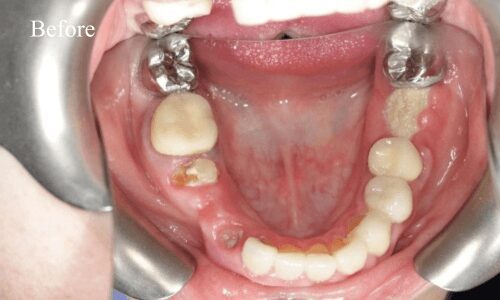

Full Mouth Rehabilitation

Full mouth rehabilitation or FMR is a restorative dental procedure which involves replacing all the teeth in the upper and lower jaws.This is a comprehensive treatment that combines general, cosmetic and restorative dentistry. This means you may have to get dental crowns, implants and whitening done at the same time to bring back the original strength, functionality, and aesthetic appeal of your teeth.